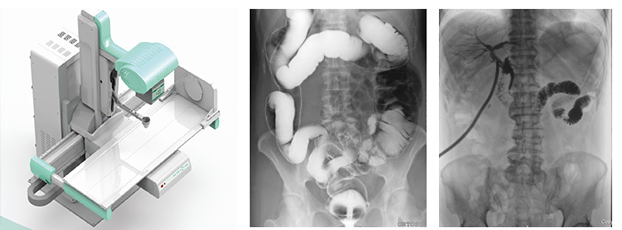

多功能動態dr由動態平板探測器、高壓發生器、球管、運動機架、計算機與圖像處理與傳輸系統組成,與傳統數字化X線攝影技術相比,動態多功能dr攝影能在一個時間單位內低劑量高速獲得多幀X線影像,通過圖像算法處理系統后,極速輸出一段連續動態影像(運動),實現所見即所得。

多功能動態dr是集合拍片,透視,造影三種功能為一體的設備。可以對特殊病灶部位進行高速實時點片,捕獲高清病灶圖,降低了漏診誤診率。特別是對不能配合的患者,也能進行快速高效的檢查,大大減輕了患者的痛苦。